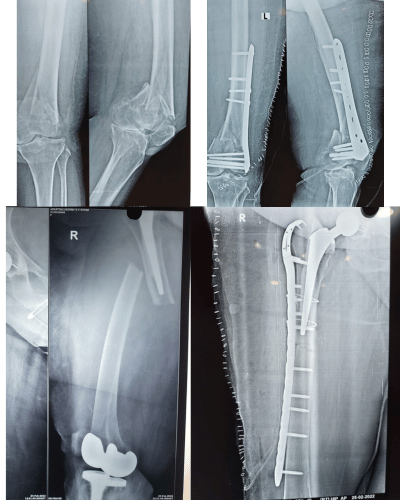

Our expert trauma team provides comprehensive fracture and injury management with advanced techniques and personalized care.

Simple Fractures – Treated effectively with splinting or plaster of paris application 24X7

Compound Fractures – Specialized care to prevent infection and restore function.

Major Fractures – Multimodal treatment to stabilise the patient immediately and team work to stabilise the fractures and other associated injuries (Head injuries, abdominal injuries)

Periprosthetic Fractures – Expert management of fractures around Prosthetic joints .

Fractures in Children – Gentle, specialized treatment for growing bones including surgical and non surgical methods.